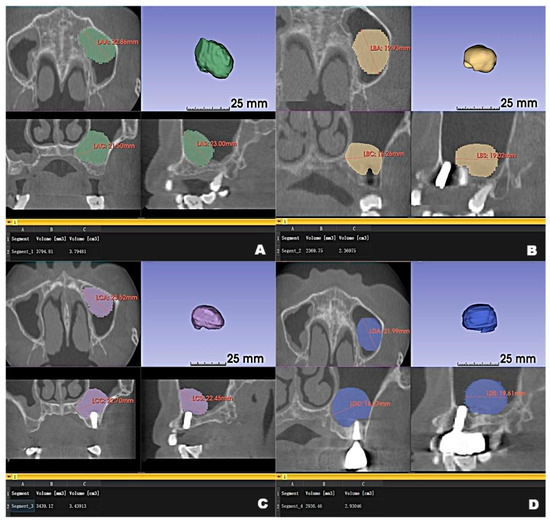

Figure 3.

Preoperative CBCT (A) and follow-up CBCT images (6 months (B), 12 months (C), and 22 months (D)) of the patient’s left maxillary antral pseudocyst in the axial, coronal, and sagittal planes.

Although the final crown restoration (second procedure) was planned for 6 months after the first procedure, it was delayed until 10 months because of an outbreak of COVID-19. A CBCT scan at the 6-month follow-up showed that the implants had been correctly placed in the augmented sinus, resulting in osseointegration without mobility (Figure 3B). CBCT scans at 12 months and 22 months showed stable bone levels around the implants (Figure 3C,D). The patient reported no discomfort or other complaints in relation to the implants or the maxillary sinus, and no fluid leakage was evident on the incision line during follow-up. However, a comparison of the preoperative CBCT scans with the postoperative scans conducted at 6, 12, and 22 months revealed pseudocyst drift in the left maxillary sinus (Figure 4). At 6 months after surgery, the pseudocyst had moved posterolaterally from the preoperative position near the anterior medial maxillary sinus, then returned to its original position at 12 months. However, it had remigrated to the posterolateral position at 22 months.